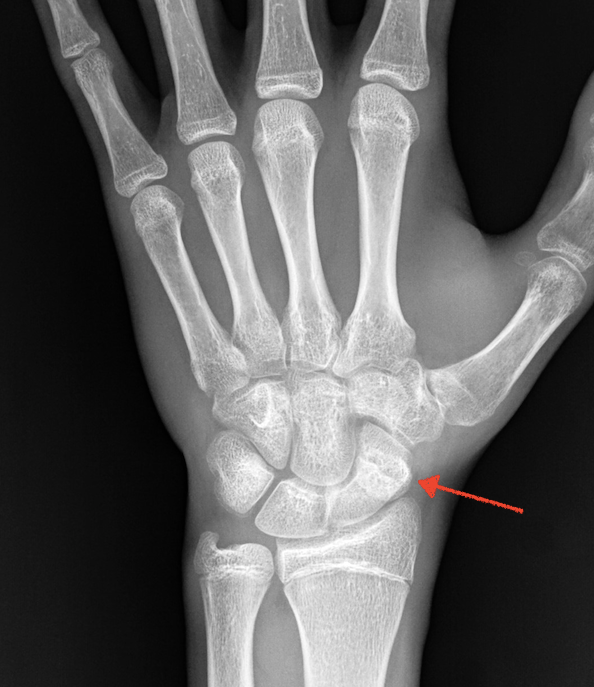

Le fratture anche per banali traumi sono frequenti, come frequenti sono le fratture misconosciute che non vengono diagnosticate e trattate tempestivamente e possono portare ad una pseudoartrosi, ossia un quadro cronico di mancata consolidazione causa sia di dolore, ma soprattutto di alterata funzionalità del polso i cui movimenti continuano in un quadro di nono coordinazione con le altre ossa. Questo nel tempo porta a delle alterazioni artrosiche con coinvolgimento di altre zone del carpo fino ad una artrosi diffusa.